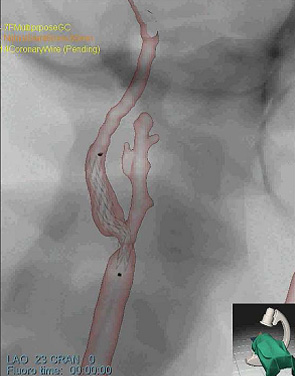

研究使用SimbionixANGO导师TM以色列dd站ANGO导师TM综合软件硬件内置模拟平台1a)模拟干扰程序基于诊断CTA和脉冲模拟模型支持实事求是插管操作反馈1b)并创建连续X射线成像、froscicC-arm定位和模拟反射剂注入2a-c)详情见http://www.simbionix.com

模拟模型直接转至SimbionixANGO导师TM模拟平台然后我们执行常用干预放射程序,如导管插入和操作、气球定位和放大,并插入病人专用模型微博2a-c显示样本快照模拟

模拟无缺陷并成功实时运行超过一小时用户报告大现实主义和优异总体经验,大大优于前人工生成模型相似经验模拟实验是定性和初步性实验,它证明实际病人切片干扰模拟CTA临床扫描